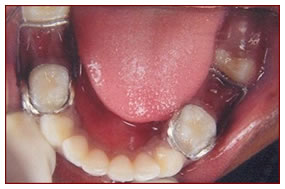

Pulpotomy ,Pulpectomy & SS Crown

All severely damaged milk teeth are saved by this procedure wherein the decayed living tissue is removed and filled with restorative material.

The teeth that are saved by this method is further strengthened by capping with metal crowns.